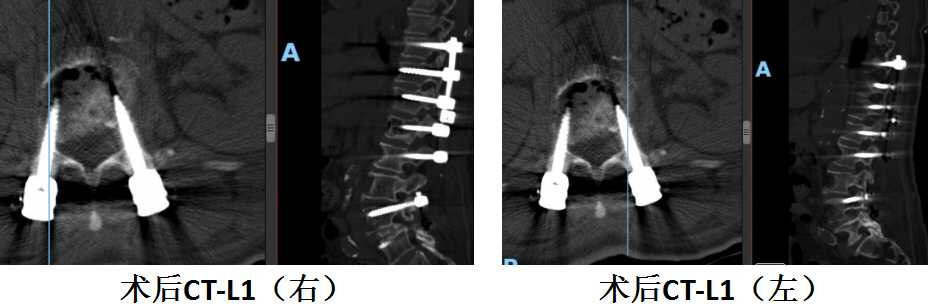

陈奶奶术后腰1水平螺钉位置良好,椎管减压彻底

陈奶奶术后腰2水平螺钉位置良好